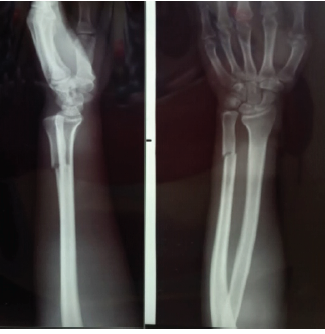

Isolated Distal Ulna shaft fracture with Distal Radioulnar Joint dislocation or Reverse Galeazzi Pattern: A Case Report with Literature Review

Ranjeet Choudhary , Ramesh Negi , Devender Kasotya , Harshit Verma , Sukhmin Singh

………………………………p.168-172